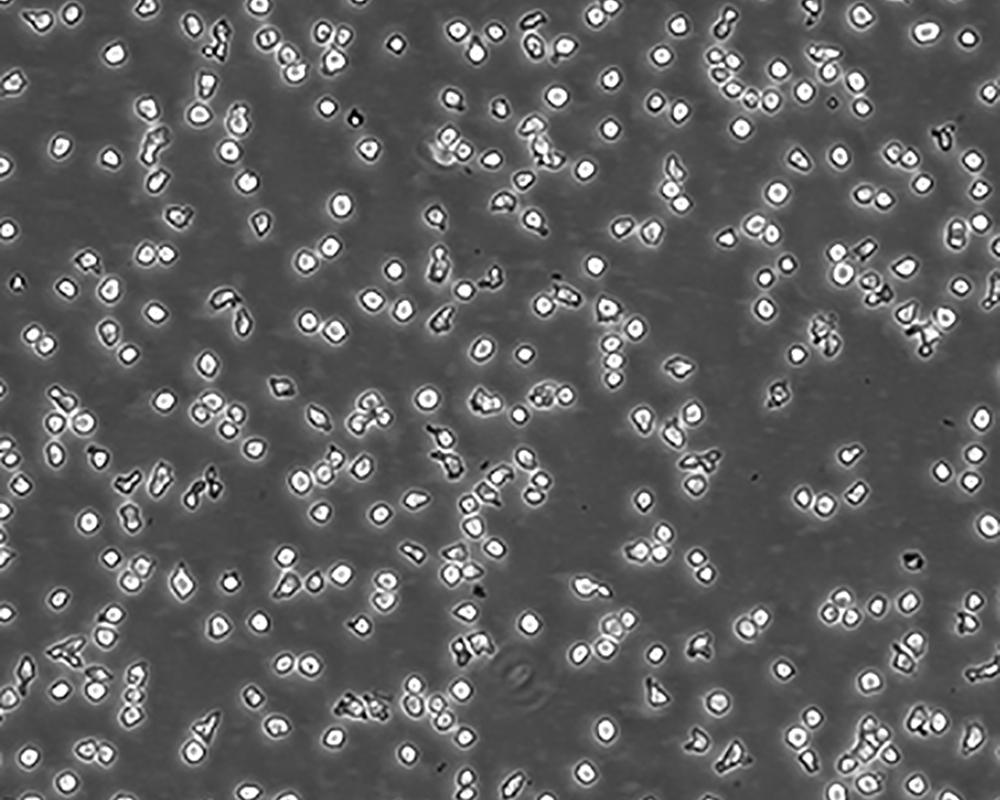

中文名稱 人Burkitt's淋巴瘤細胞

生長特性 suspension

形態(tài)特征 lymphoblast

細胞描述 R該細胞源自Burkitt's淋巴瘤患者的B淋巴細胞,EBNA、Fc陰性。